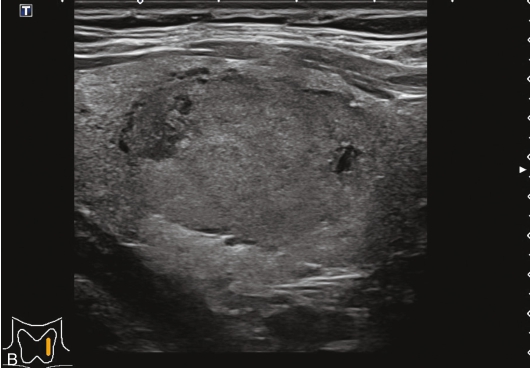

甲状腺左叶中下部见一混合回声结节,边界清,形态规则,中心部可见斑状强回声,CDFI显示周边可见环状血流信号,其内可见丰富血流信号,见图1-3-18。

该结节早于周围腺体组织增强,结节内部呈高增强表现,可见部分无增强区;结节晚于周围腺体组织消退,仍呈高增强表现;结节周边可见均匀高增强环,甲状腺被膜未见明显中断,见图1-3-19、ER1-3-9。

(1)结节增强早期早于腺体增强或与腺体同步增强,增强晚期晚于腺体消退或与腺体同步消退。

(2)结节内部呈均匀或不均匀弥漫性等增强或高增强,增强水平通常高于周围腺体。

(3)结节与周围腺体分界清晰,形态较规则。

(4)部分结节周边可见均匀高增强环。

(5)结节周边被膜连续完整。

甲状腺滤泡性腺瘤通常为富血供病灶,其增强水平等于或高于周围腺体,并呈现“早增强,晚消退”的特点,重点需要与滤泡性腺癌鉴别,腺瘤多边界清晰、形态较规则,造影时结节周围的高增强环厚薄一致、较为均匀,结节周边被膜连续完整、无浸润表现,颈部淋巴结无异常肿大等。而滤泡性腺癌边界不清、呈浸润性生长表现,周边高增强环消失或厚薄不均,如发现颈部异常肿大淋巴结及被膜连续性中断等,需要高度警惕甲状腺恶性肿瘤。

图1-3-18 甲状腺滤泡性腺瘤常规超声声像图

A.甲状腺左叶纵切面超声图像;B.结节内部点状及斑状强回声;C.CDFI血流图